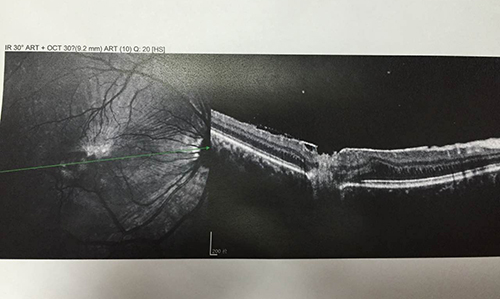

这是一个正常的黄斑区OCT图像 凹陷处平滑

这是激光伤的OCT图像 凹陷处有明显褶皱